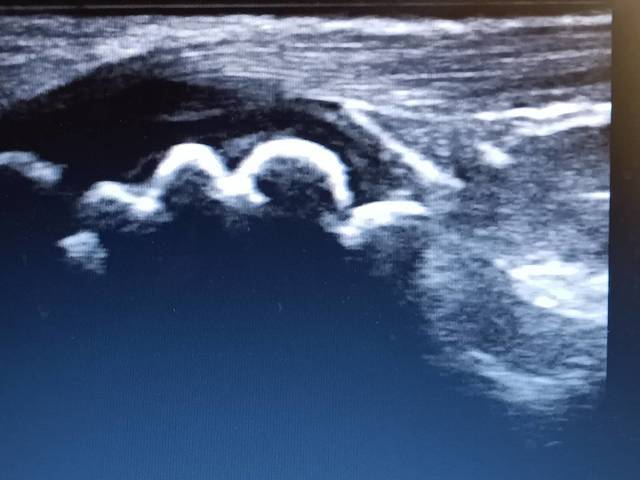

小学生中学年から中学生にかけて成長期の前の段階から、激しいスポーツをしている子供がなりやすい疾患です。足首や股関節の柔軟性が低下している子供たちが多いため、足の指に体重がのらず(浮指)かかとに負担がかかって、軟骨部分が痛くなります。エコー画像で、ギザギザの軟骨が描写されることがあします